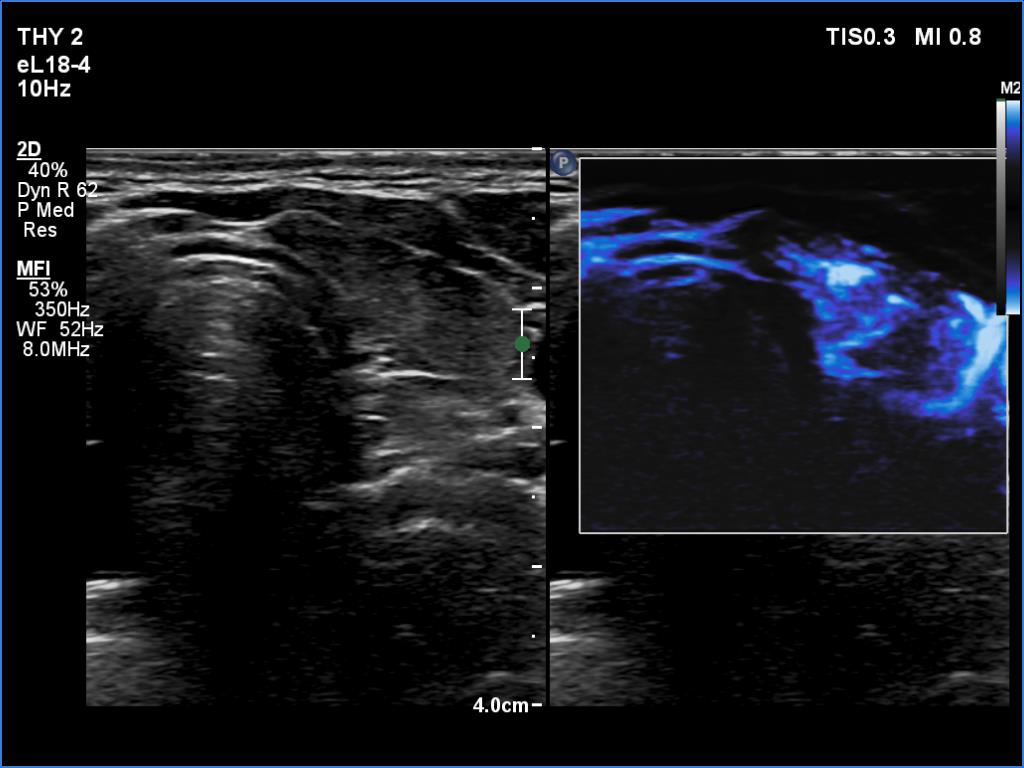

Parathyroid lesions - case 1521 (ultrasonographic picture 10)

Left lobe, transverse scan, microflow imaging.